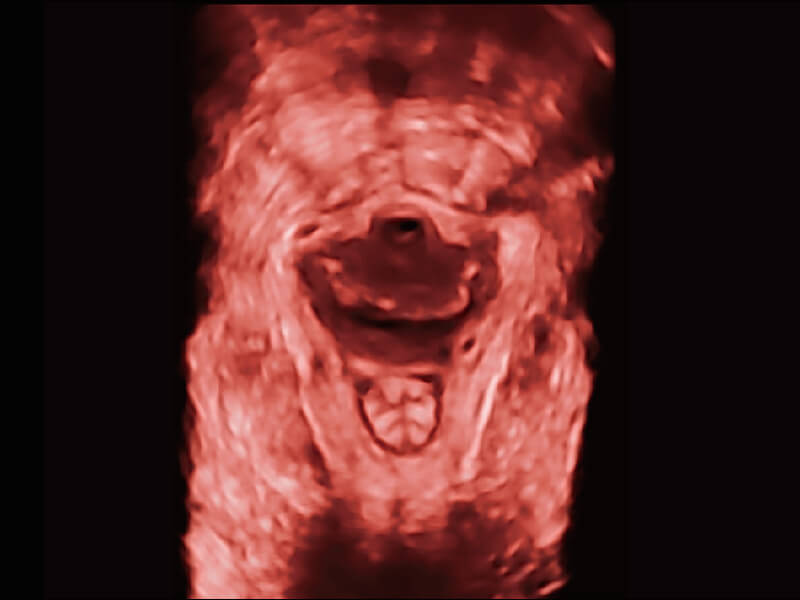

S60探头工艺,从前端信号处理每一个环节采集无损声学数据,真实还原组织原貌,再现解剖细节。